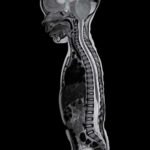

MRI is a versatile imaging technique that can be used to examine various parts of the body, including the brain, spine, joints, abdomen, and pelvis.

It is particularly useful for visualizing soft tissues like organs, muscles, tendons, ligaments, and the central nervous system. Unlike X-rays or CT scans, MRI does not use ionizing radiation, making it a safer option for many patients, including pregnant women and children. MRI is a valuable tool in modern medicine, providing non-invasive and detailed imaging that helps healthcare professionals make accurate diagnoses and develop effective treatment plans for patients.